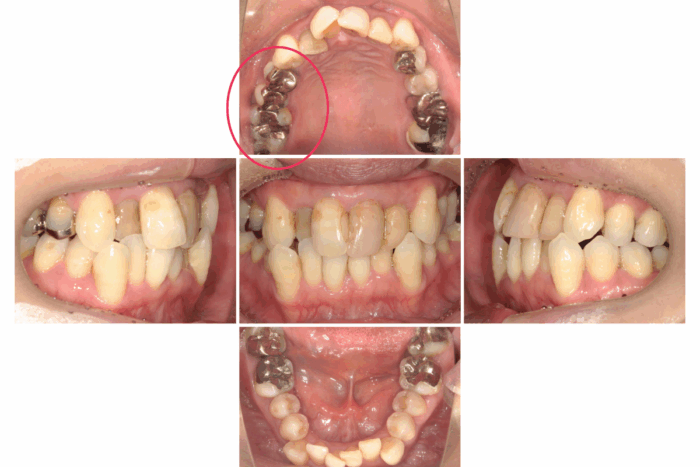

患者さま:40代女性/右上4・5・6番にメタルブリッジ

主訴:歯並びのガタガタが気になる

年齢と銀歯がたくさん入っているので、矯正できるか気にされていました。ブリッジの部分の歯根状態に問題がなかったのでブリッジはそのまま、マウスピース矯正装置(インビザライン)で矯正治療を行いました。

- 【症例詳細】

- 主訴:ガタガタが気になる

- 診断名:叢生

- 初診時年齢:49歳

- 使用装置:マウスピース矯正装置(インビザライン)

- 抜歯部位:なし

- 治療期間:1年2ヶ月

- 費用:¥865,000(税込¥951,500)

- リスク・副作用:痛み、歯根吸収、歯肉退縮、むし歯、後戻り